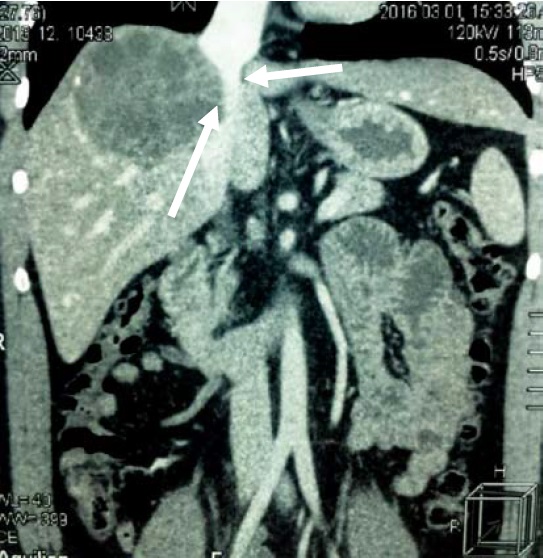

Для дальнейшего углубленного обследования и определения тактики лечения переведен в клинику военно-морской хирургии Военно-медицинской академии имени С.М. Кирова. В клинике выполнено комплексное клинико-лучевое обследование. При мультиспиральной компьютерной томографии (МСКТ) головы, грудной клетки, брюшной полости подтверждено наличие эхинококковой кисты правой доли печени около 10 см, которая сдавливает нижнюю полую вену (рис. 2, 3). В других органах и тканях эхинококк не выявлен. Пациент проконсультирован паразитологом – выставлен диагноз: эхинококковая киста печени.

Рис. 2. МСКТ эхинококковой кисты (многокамерная киста в правой доле диаметром 10 см)

Рис. 3. Компрессия нижней полой вены кистой